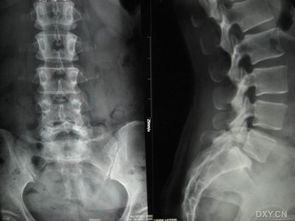

慢性腰痛是腰椎滑脫的主要癥狀。腰椎滑脫是指腰椎椎體間部分或全部錯位的一種疾患,一般是上位椎體向前滑移。臨床上分為真性滑脫和假性滑脫。治療前要明確是屬于哪種類型的滑脫。因此除了拍腰椎正側位片外,還應該拍腰椎雙斜位片,必要時還要行CT和核磁共振檢查以明確是否有神經根的壓迫。

當發(fā)現腰部不適時,應當前往醫(yī)院就診,一般的輔助檢查不很昂貴,普通的X線平片或者的腰椎的雙斜位像就可以明確診斷。但是,當病情復雜如合并腰椎間盤突出、腰椎管狹窄或排除腰椎病變時,應該進一步拍腰椎過伸過屈片以觀察滑脫椎體的穩(wěn)定性,另外還需做CT、核磁共振等檢查以了解神經根受壓情況。